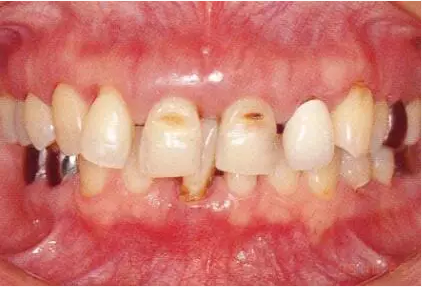

上頜前牙部前突在牙周外科處理以后得到改善的病例

1.png

▲圖16-1~3

11.png

▲圖16-4

▲圖16-1~4 56歲,女性?;加腥谘乐苎浊蚁骂M磨牙區(qū)缺失,可以看到上頜前牙區(qū)有前突的現(xiàn)象。左上1和右上1無法保留。